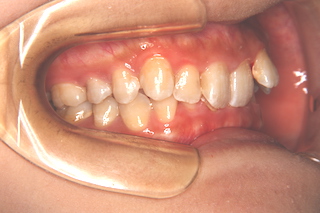

噛み合わせが深く,下の前歯が見えません!

側面・・この角度でも,下の前歯は見えません